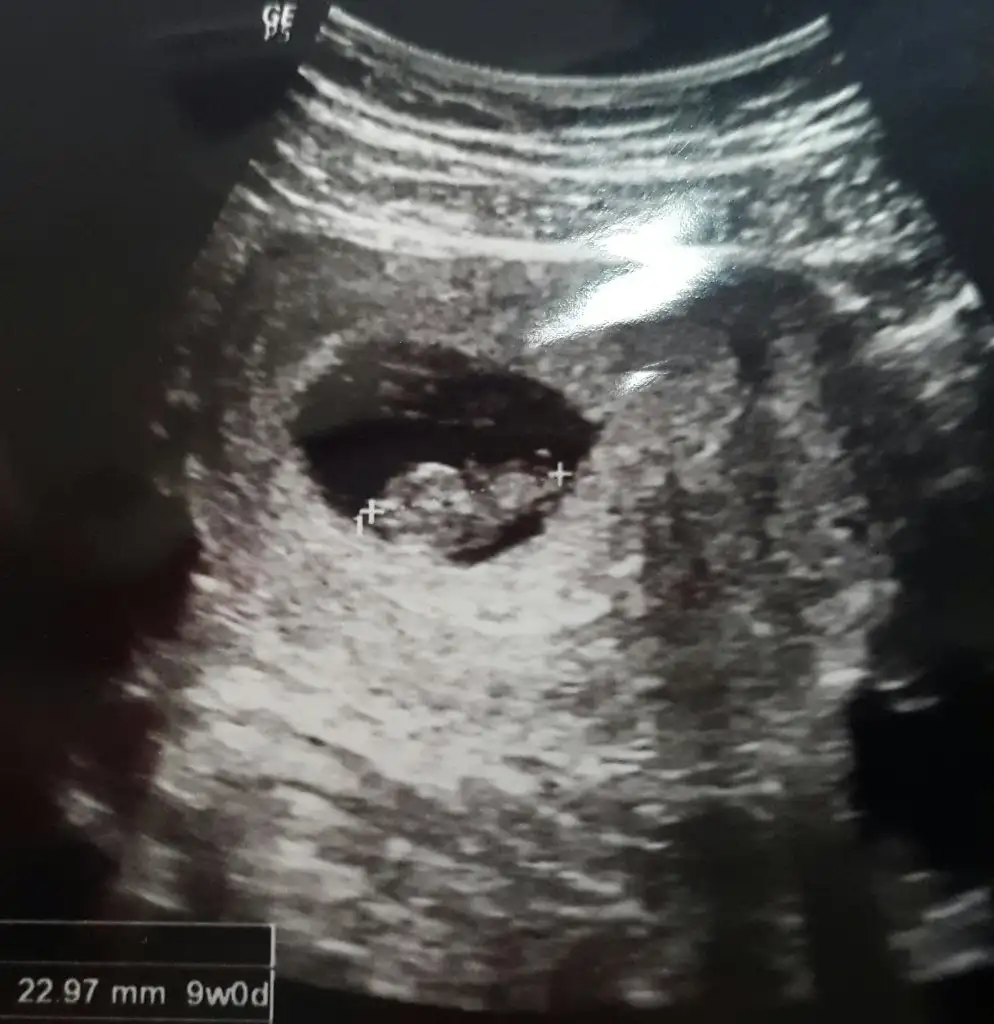

Kese solda bebek solda %70 erkek diyebilirimEki Görüntüle 1484556 Eki Görüntüle 1484558 kızlar 8haftalık yorumlarmısınız

Canım inşallah bir kızım var buda erkek olsa ne güzel olur ay inşallah hiç umudum yok ama inşallah diyorumKese solda bebek solda %70 erkek diyebilirim

Bence erkek canim benim ultrason fotomda ayni boyleydi hayirlisiyla kucagina alirsin insallahEki Görüntüle 1484556 Eki Görüntüle 1484558 kızlar 8haftalık yorumlarmısınız

Kese solda bebek solda %70 erkek diyebilirim

Cnm senin bebek çok güzel şekillenmiş 9. Haftaya göre valla başka bişeyde olabilir ama ben bu bebeğe erkek diyorum9.haftada yorumlar mısınız?

Cnm senin bebek çok güzel şekillenmiş 9. Haftaya göre valla başka bişeyde olabilir ama ben bu bebeğe erkek diyorum

Daha hiç bişey netdeyil ama sadece keseye göre söylüyorum kızKızlar benim son adet tarihi 21 Şubat şu an 6+6 ilk ultrason görüntüleri tahminlerinizi bekliyorumm